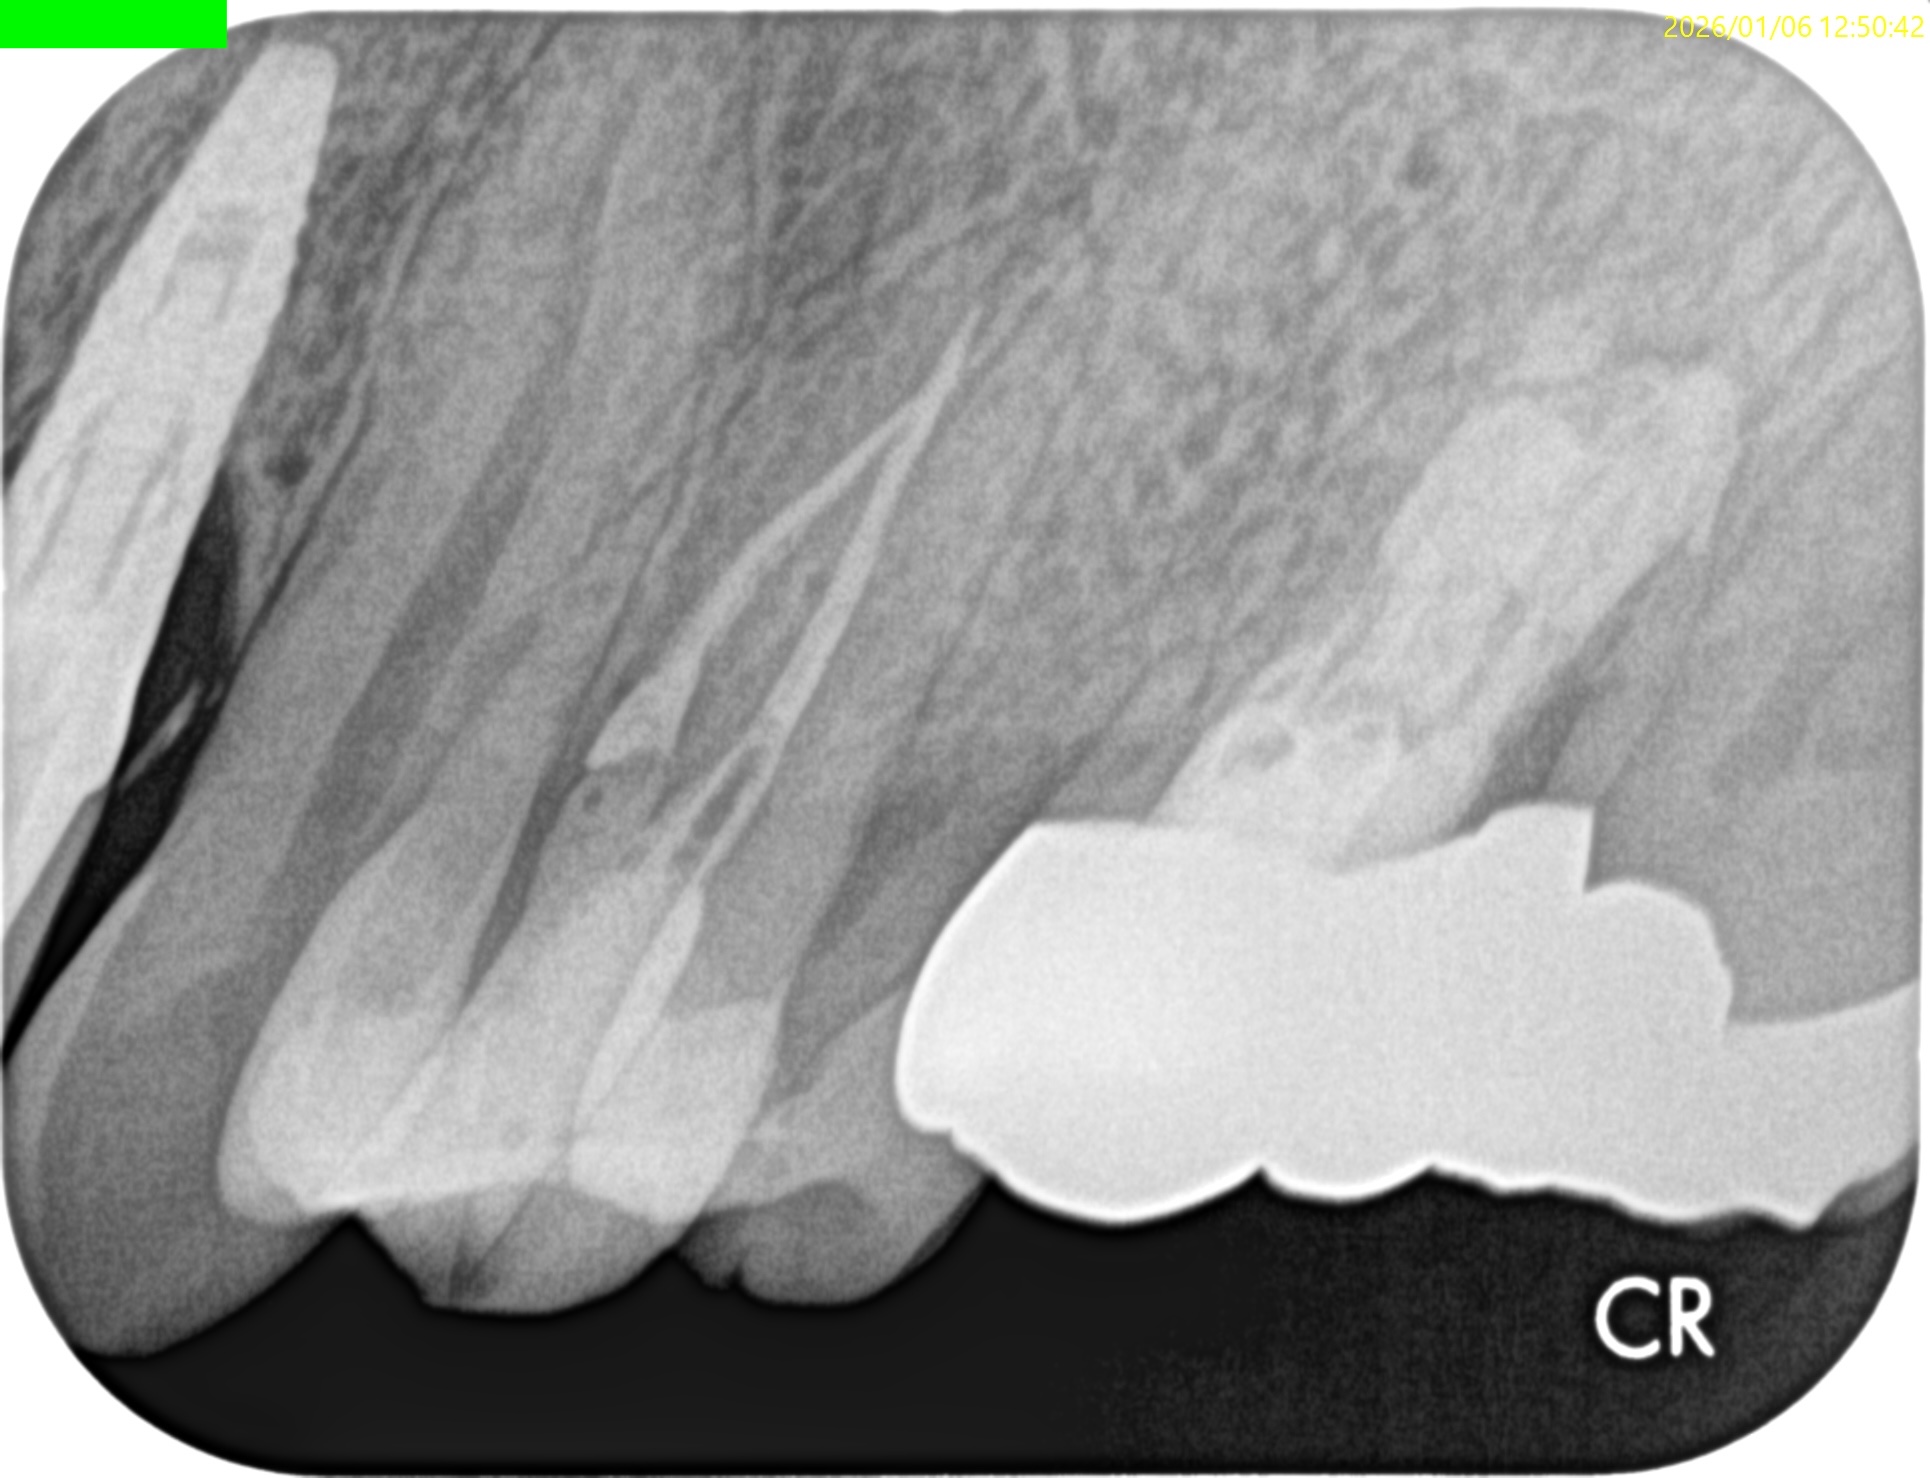

Pre-op Endo test(2026.1.6)

#11 Cold+1/2, Perc.(-), Palp.(-), BT(-), Perio probe(WNL), Mobility(WNL)

#12 Cold NR/20, Perc.(±), Palp.(-), BT(±), Perio probe(WNL), Mobility(WNL)

#13 Cold+2/2, Perc.(-), Palp.(-), BT(-), Perio probe(WNL), Mobility(WNL)

#12がCold testに反応しない。

この歯が怪しい。

Pre-op Endo Diagnosis(2026.1.6)

Pulp Dx: Pulp Necrosis

Periapical Dx: Normal apical tissues

Recommended Tx: RCT

また、治療前のCBCTで2根管性のことから合流部位の確認をいつものように行った。